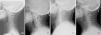

El 78% eran mujeres, la edad media fue 58,5±15 años. Los cuatro grupos eran homogéneos en cuanto a sexo y edad y el análisis estratificado no mostró diferencias (p=0,2 y p=0,06, respectivamente), solo una tendencia a su mayor presencia en ancianos del grupo CM. El 51% presentaron EO, un 23% en el grupo CM y un 60% en las enfermedades inflamatorias (70% EspA, 70% AP y 40% AR), siendo el EO estadísticamente significativo en enfermedades reumáticas inflamatorias (p<0,001). Se alcanzó un acuerdo sustancial global (89%) y casi perfecto en EspA y AP (97%). En términos de descripción macroscópica, se observaron diferentes morfologías de EO, más grueso en los grupos de EspA y AP y más fino en el grupo de AR (fig. 1).